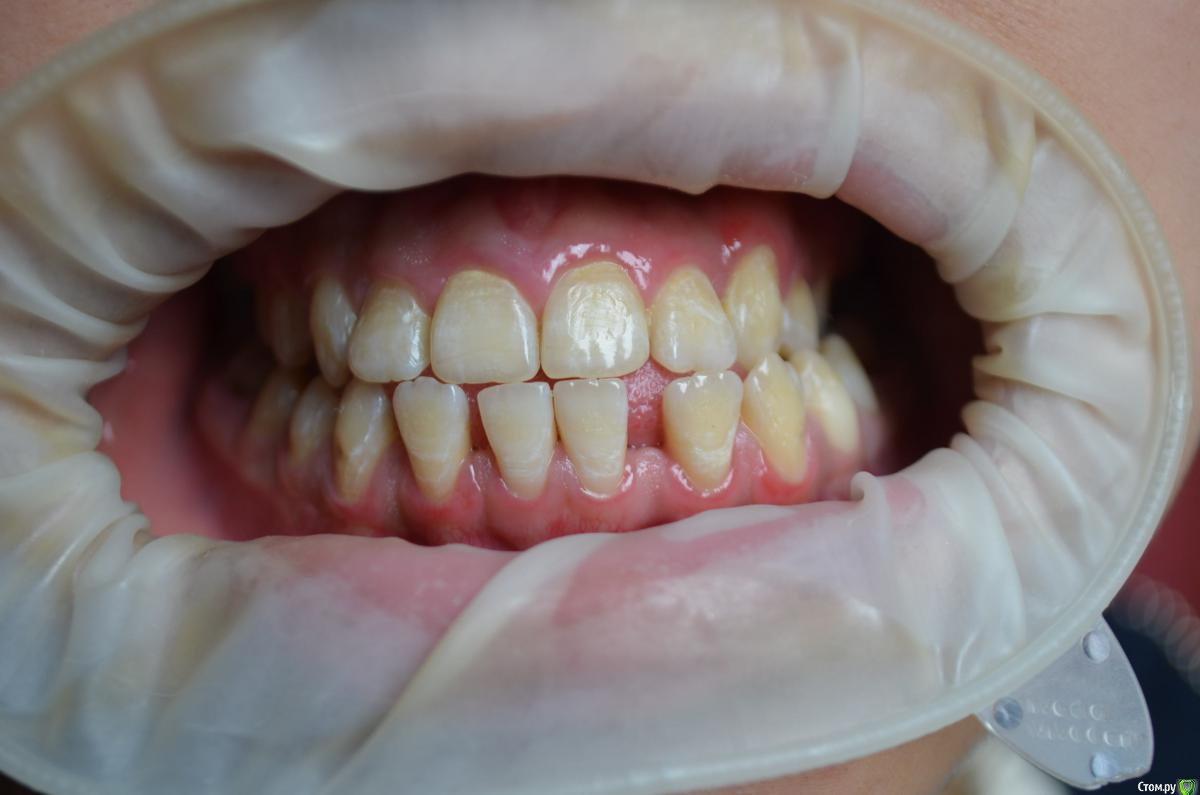

Пациентке 16 лет носила брекеты 4 года (переносила), нижний фронт зубов подвижен, слизистая воспалена, тремы на н.ч, множественный кариес под брекетами после снятия, сейчас на этапе эндолечения. Помогите советами как правильно и с чего начать , на в.ч. поставил ретейнер, на нижней пока идет терапевтическое лечение. ТРГ нету